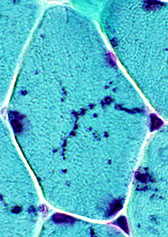

Muscle fibers usually distributed in a checkerboard pattern

- this patter is altered and causes muscle fiber grouping after nerve/muscle damage (denervation followed by re-innervation) after a period of months (signifying some kind of chronic condition)

Neurogenic Changes in Skeletal Muscle

a. Recent denervation - small, angulated of both fiber types. When

completely atrophied, appear as pyknotic nuclear clumps.

b. Chronic denervation (with reinnervation):

- Myofiber type grouping - random fiber type distribution is replaced by clustering of the same type, as a result of local reinnervation of

denervated muscle fibers by adjacent intact nerve twigs.

- Grouped myofiber atrophy - large groups of atrophic fibers as a result of increasing loss of motor units.

Denervation atrophy - affects both muscle types